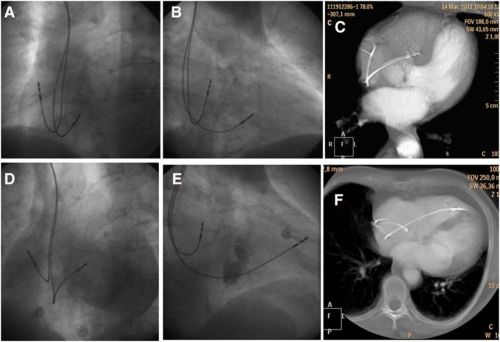

- Image courtesy: Pavel Osmancik Circulation: Arrhythmia and Electrophysiology. 2013; 6: 719-725 Fluoroscopic examples of 2 patients. One with correct lead placement in the septum (A–C) and the other with the lead placed in the anterior wall (D–F). See the similarity of the left anterior oblique 40 view, the difference of the right anterior oblique 30 and the location of the lead on computed tomography image.

What we have been thinking as mid septal pacing with LAO protocol turns out to be anterior RV pacing in 60% of times.The study showed LA0 40 view failed to differentiate anterior RV pacing from mid septal pacing .CT scan correlates have documented this . Further ,we have never given a thought to the wayward trabecuale coming across mid septal zone. It has happened time and again (Atleast i have witnessed) the lead would just fall short of IVS and get screwed in the trabeculae with high risk for dislodgement . RAO 30 view consistently separates the mid septal lead from anterior RV position.It is suggested a carefully done per-procedure echo would also be useful in locating the lead tip .